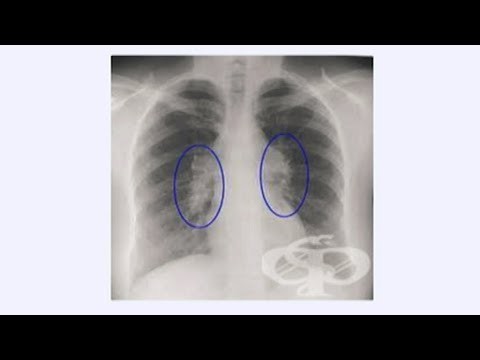

Саркоидоза - диагностика, профилактика и лечение